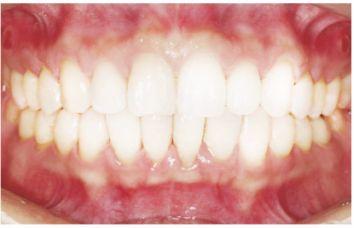

種植修復(fù)后照片